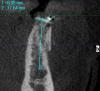

SergeyAL Опубликовано 27 мая, 2013 Поделиться Опубликовано 27 мая, 2013 у пациентки трехмерный костный дефект далее проведена трехмерная костная пластика, доступ латеральный тоннель рана ушита послойно получен хороший объем костной ткани получена костная ткань хорошего качества, хорошо кровоснабжаемая 5 Ссылка на комментарий

SergeyAL Опубликовано 30 мая, 2013 Автор Поделиться Опубликовано 30 мая, 2013 Чаще всего да, надо по кт смотреть где оптимальный блок можно забрать Ссылка на комментарий